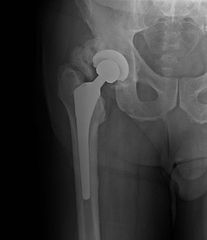

Radiographs: